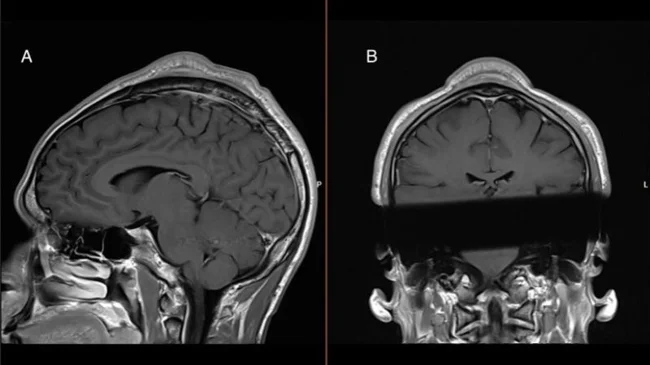

Медики исследовали выпуклость и провели структурное сканирование черепа и установили, что между кожей и черепом была зажата мягкая масса, а также то, что кожа над опухолью и кость под ней были значительно толще, чем ткани, окружающие череп.